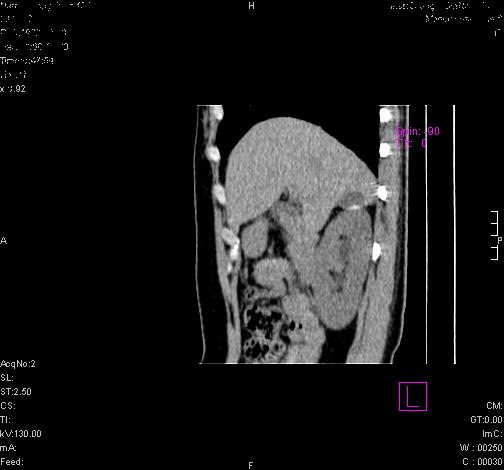

标题: CL0340:【】肾上腺囊肿,比较典型。

患者为年轻女性,查体发现右侧肾上腺囊性占位。无临床体征。

这么漂亮的图像,一看一目了然。典型的右侧肾上腺囊肿,周围有钙化。感谢搂主!

这么明显的弧形钙化,多考虑包虫病所致的寄生虫性囊肿。

右侧肾上腺囊性密度灶囊壁有钙化。考虑肾上腺囊肿,结核?